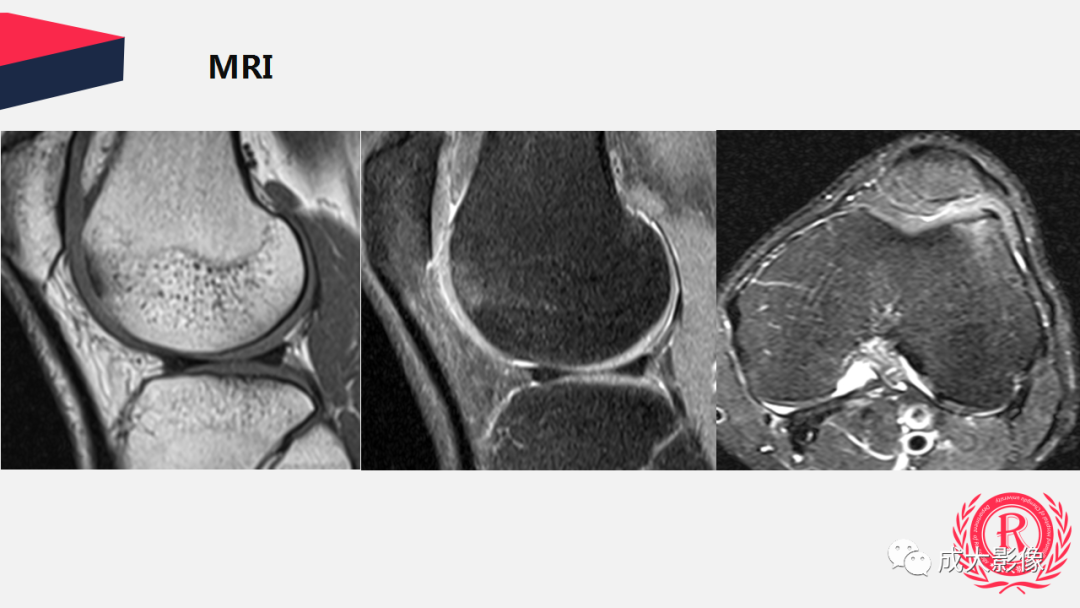

【PPT】剥脱性骨软骨炎

病例: